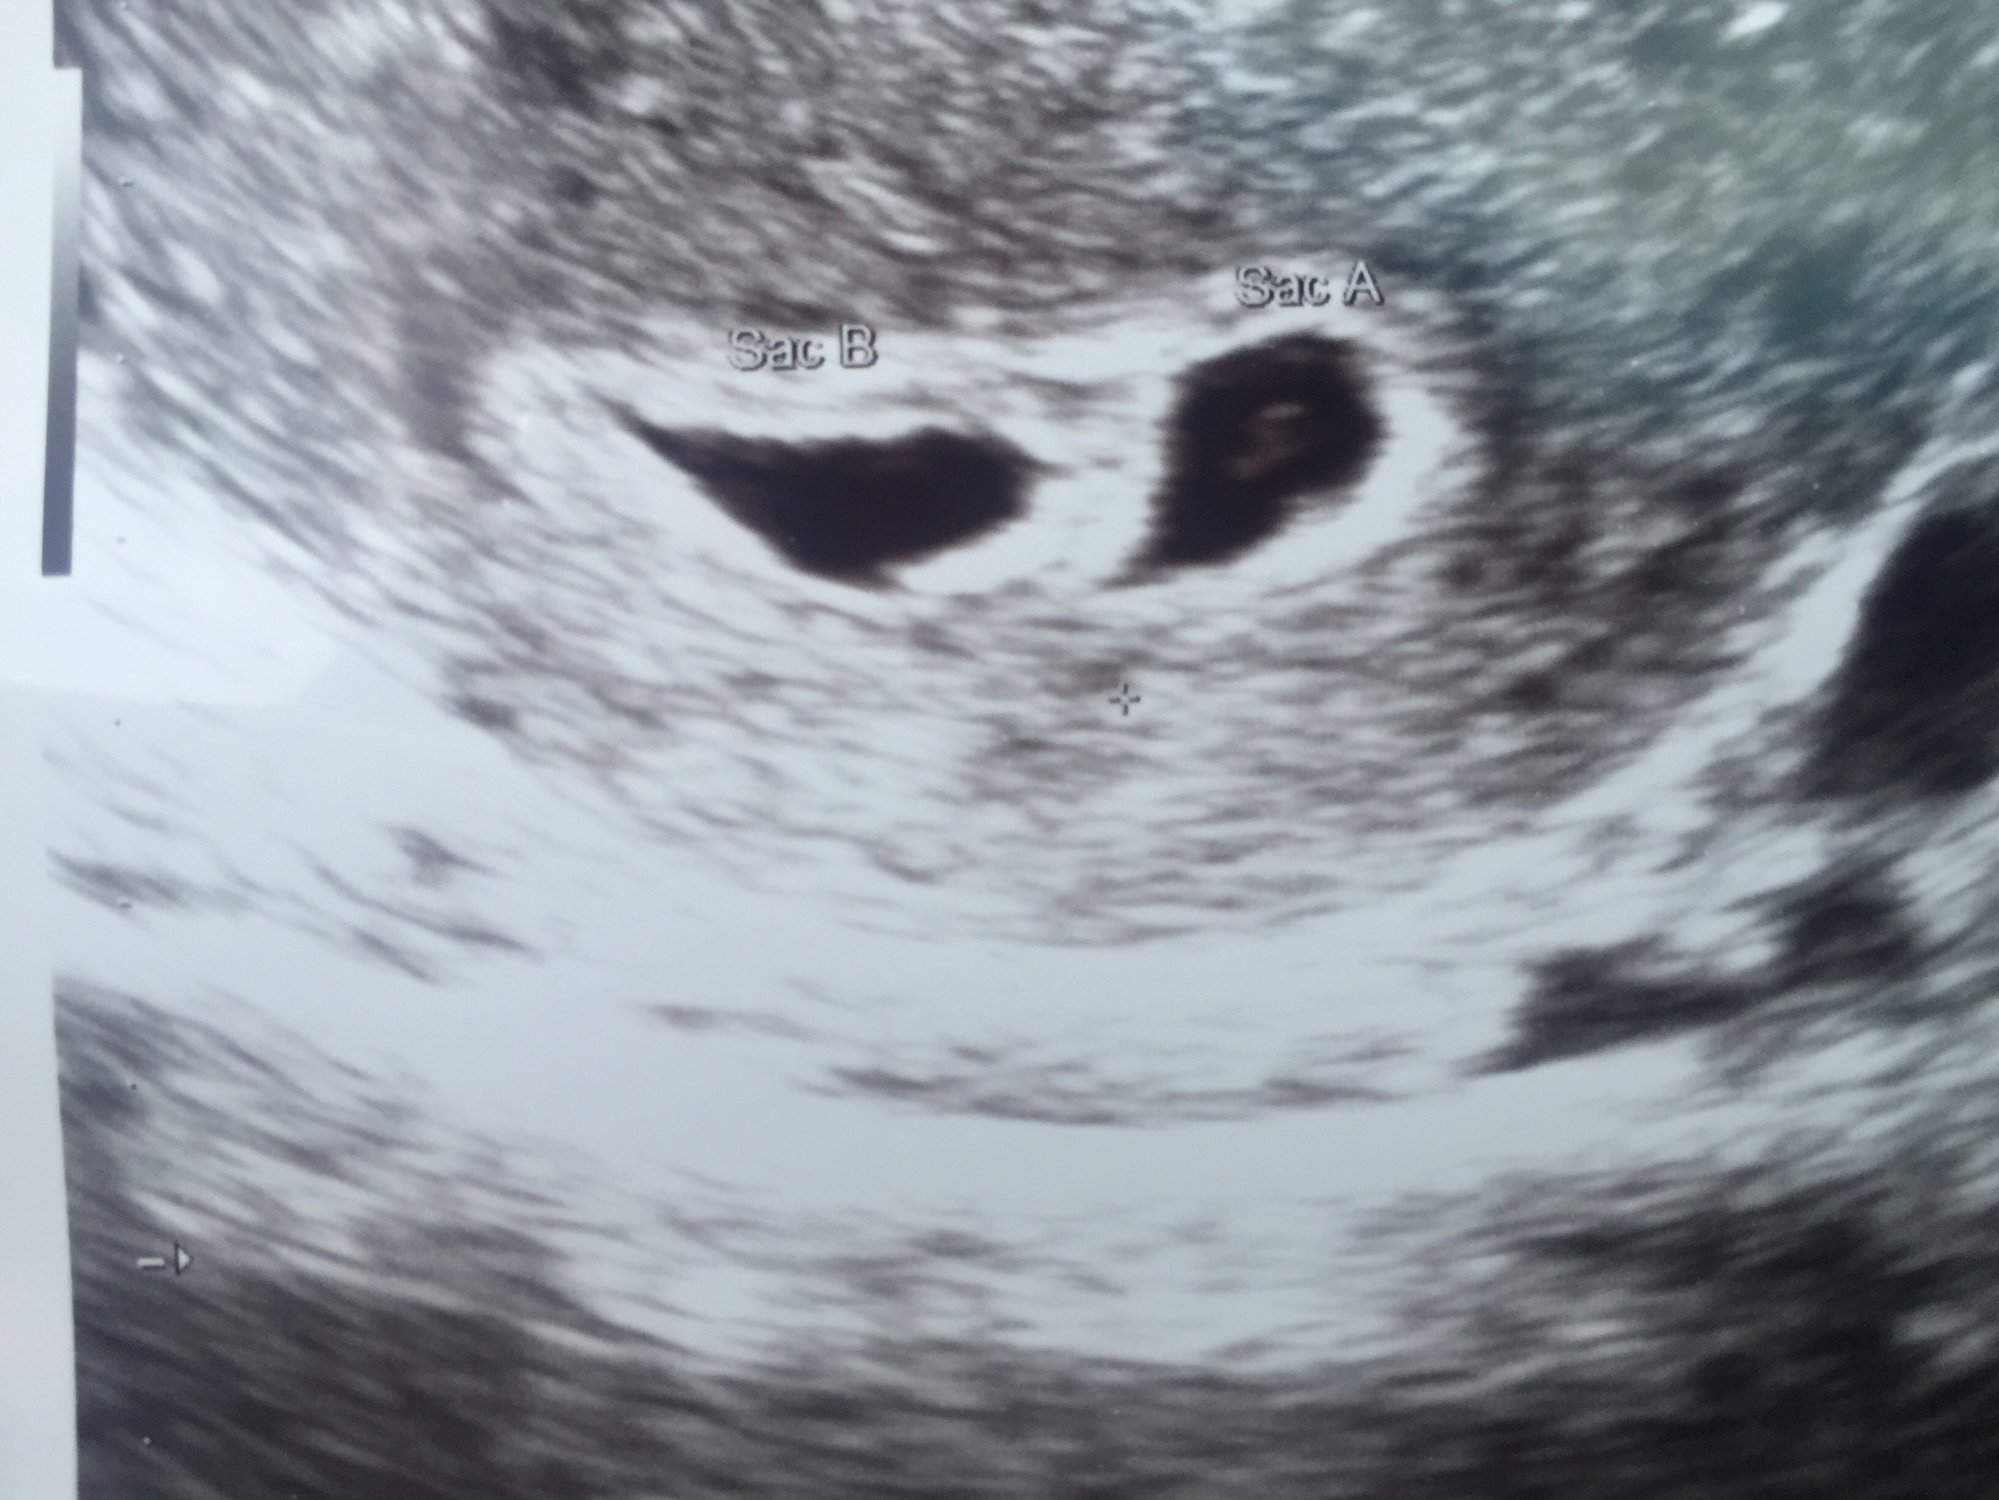

Appointment went well today and I'm measuring at 5 weeks 3 days RE said that my discharge was normal yesterday go back for my second ultrasound on Tuesday. Oh and did I mention that we are having TWINS!!!!!!

@ultratomato amazing, congratulations!! You transferred 2 I believe, correct?

@ultratomato holy crap girl!! You're having twins.